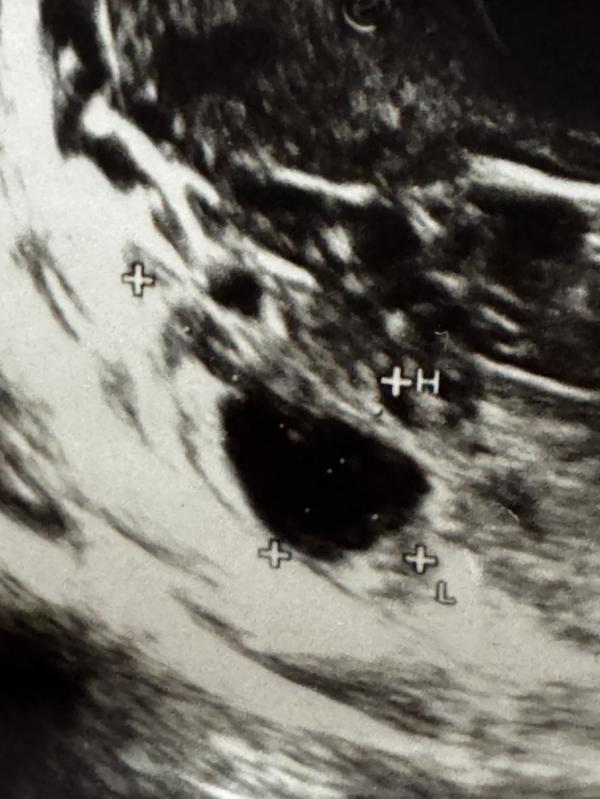

Хелп! Как вы думаете на фото фолликул несовулировавший или все таки желтое тело? 🧐

Сдайте прогестерон , будет точно ясно фолик это не лопнувший или желтое тело . А жидкость есть в позадиматочном , кровоток в нем какой ?

Жёлтое тело определяют по кровотоку в нём. Поэтому тут не понятно

Больше похоже на ЖТ, но надо кровоток смотреть.